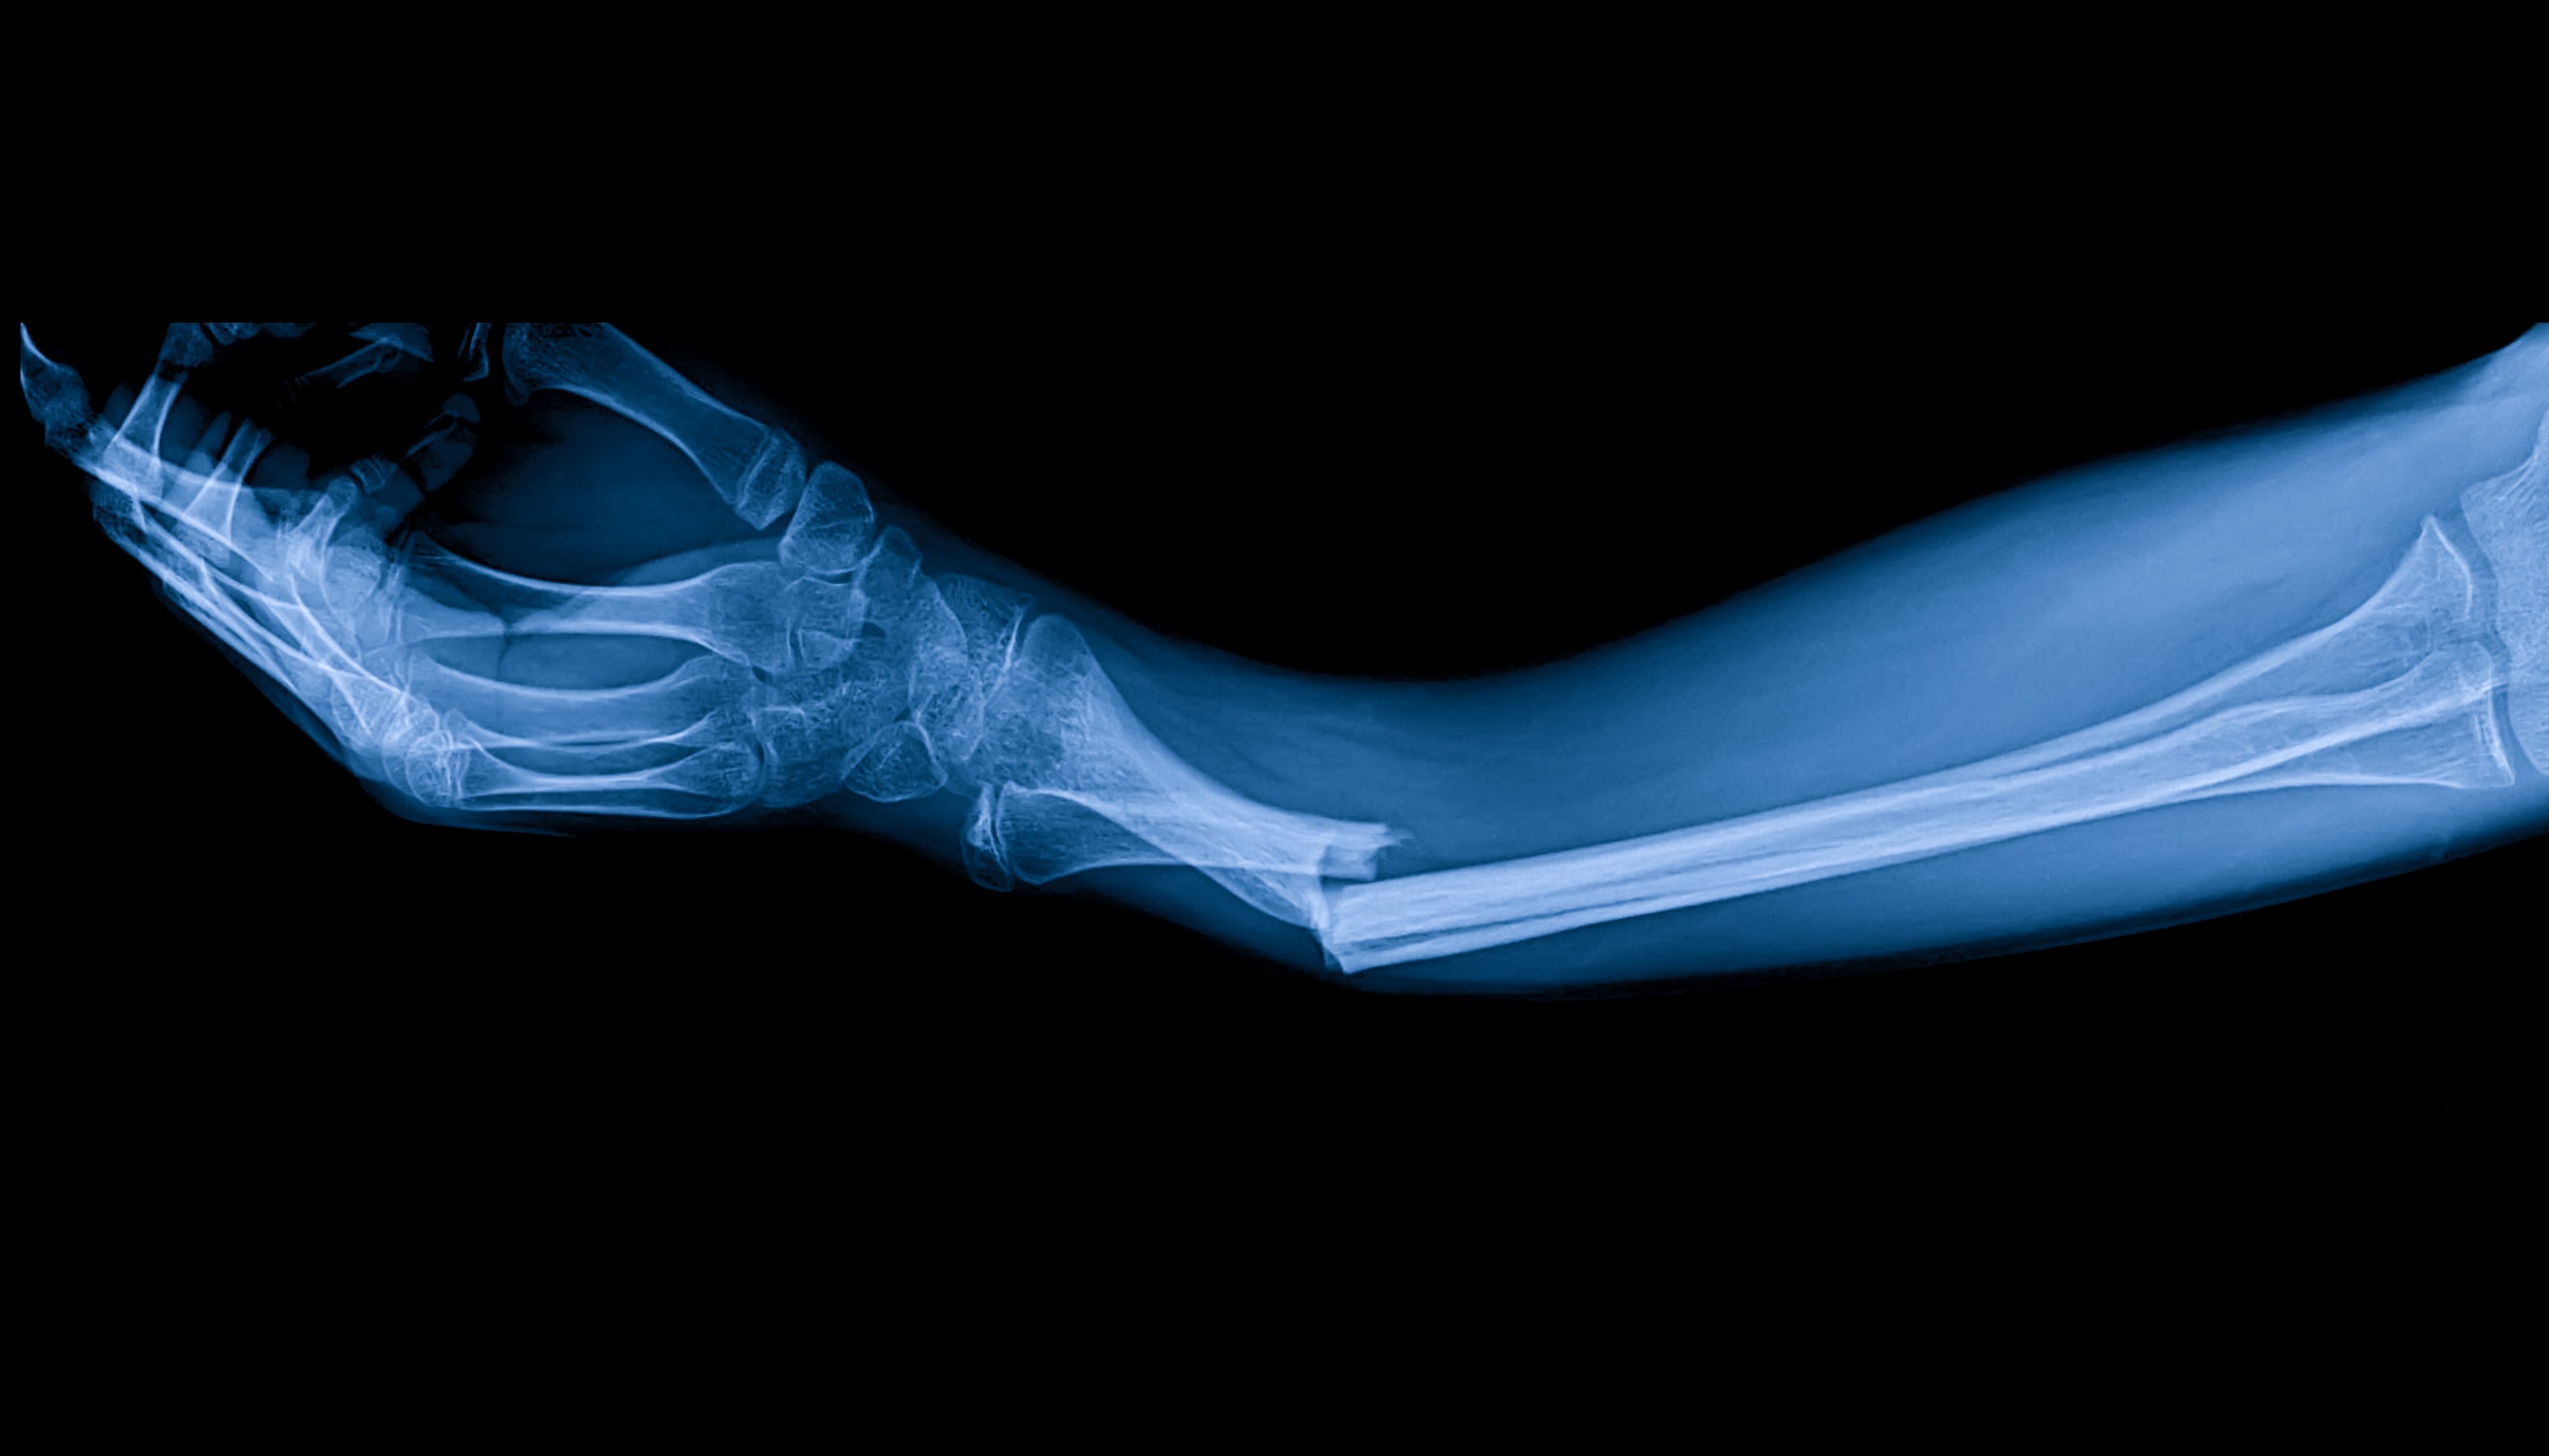

يمكن أن تنتج كسور العظام عن الحوادث أو السقوط أو الإصابات الرياضية، مما يتطلب فترة تعافي كبيرة تختلف حسب شدة الكسر وموقعه. تشمل طرق التئام العظام التقليدية التثبيت بالجبائر أو الجبائر، وأحياناً التدخلات الجراحية. يكمّل العلاج بالترددات الكهرومغناطيسية الكهربائية الخاصة هذه الطرق من خلال تحفيز الإصلاح الخلوي ونمو العظام على المستوى الجزيئي.